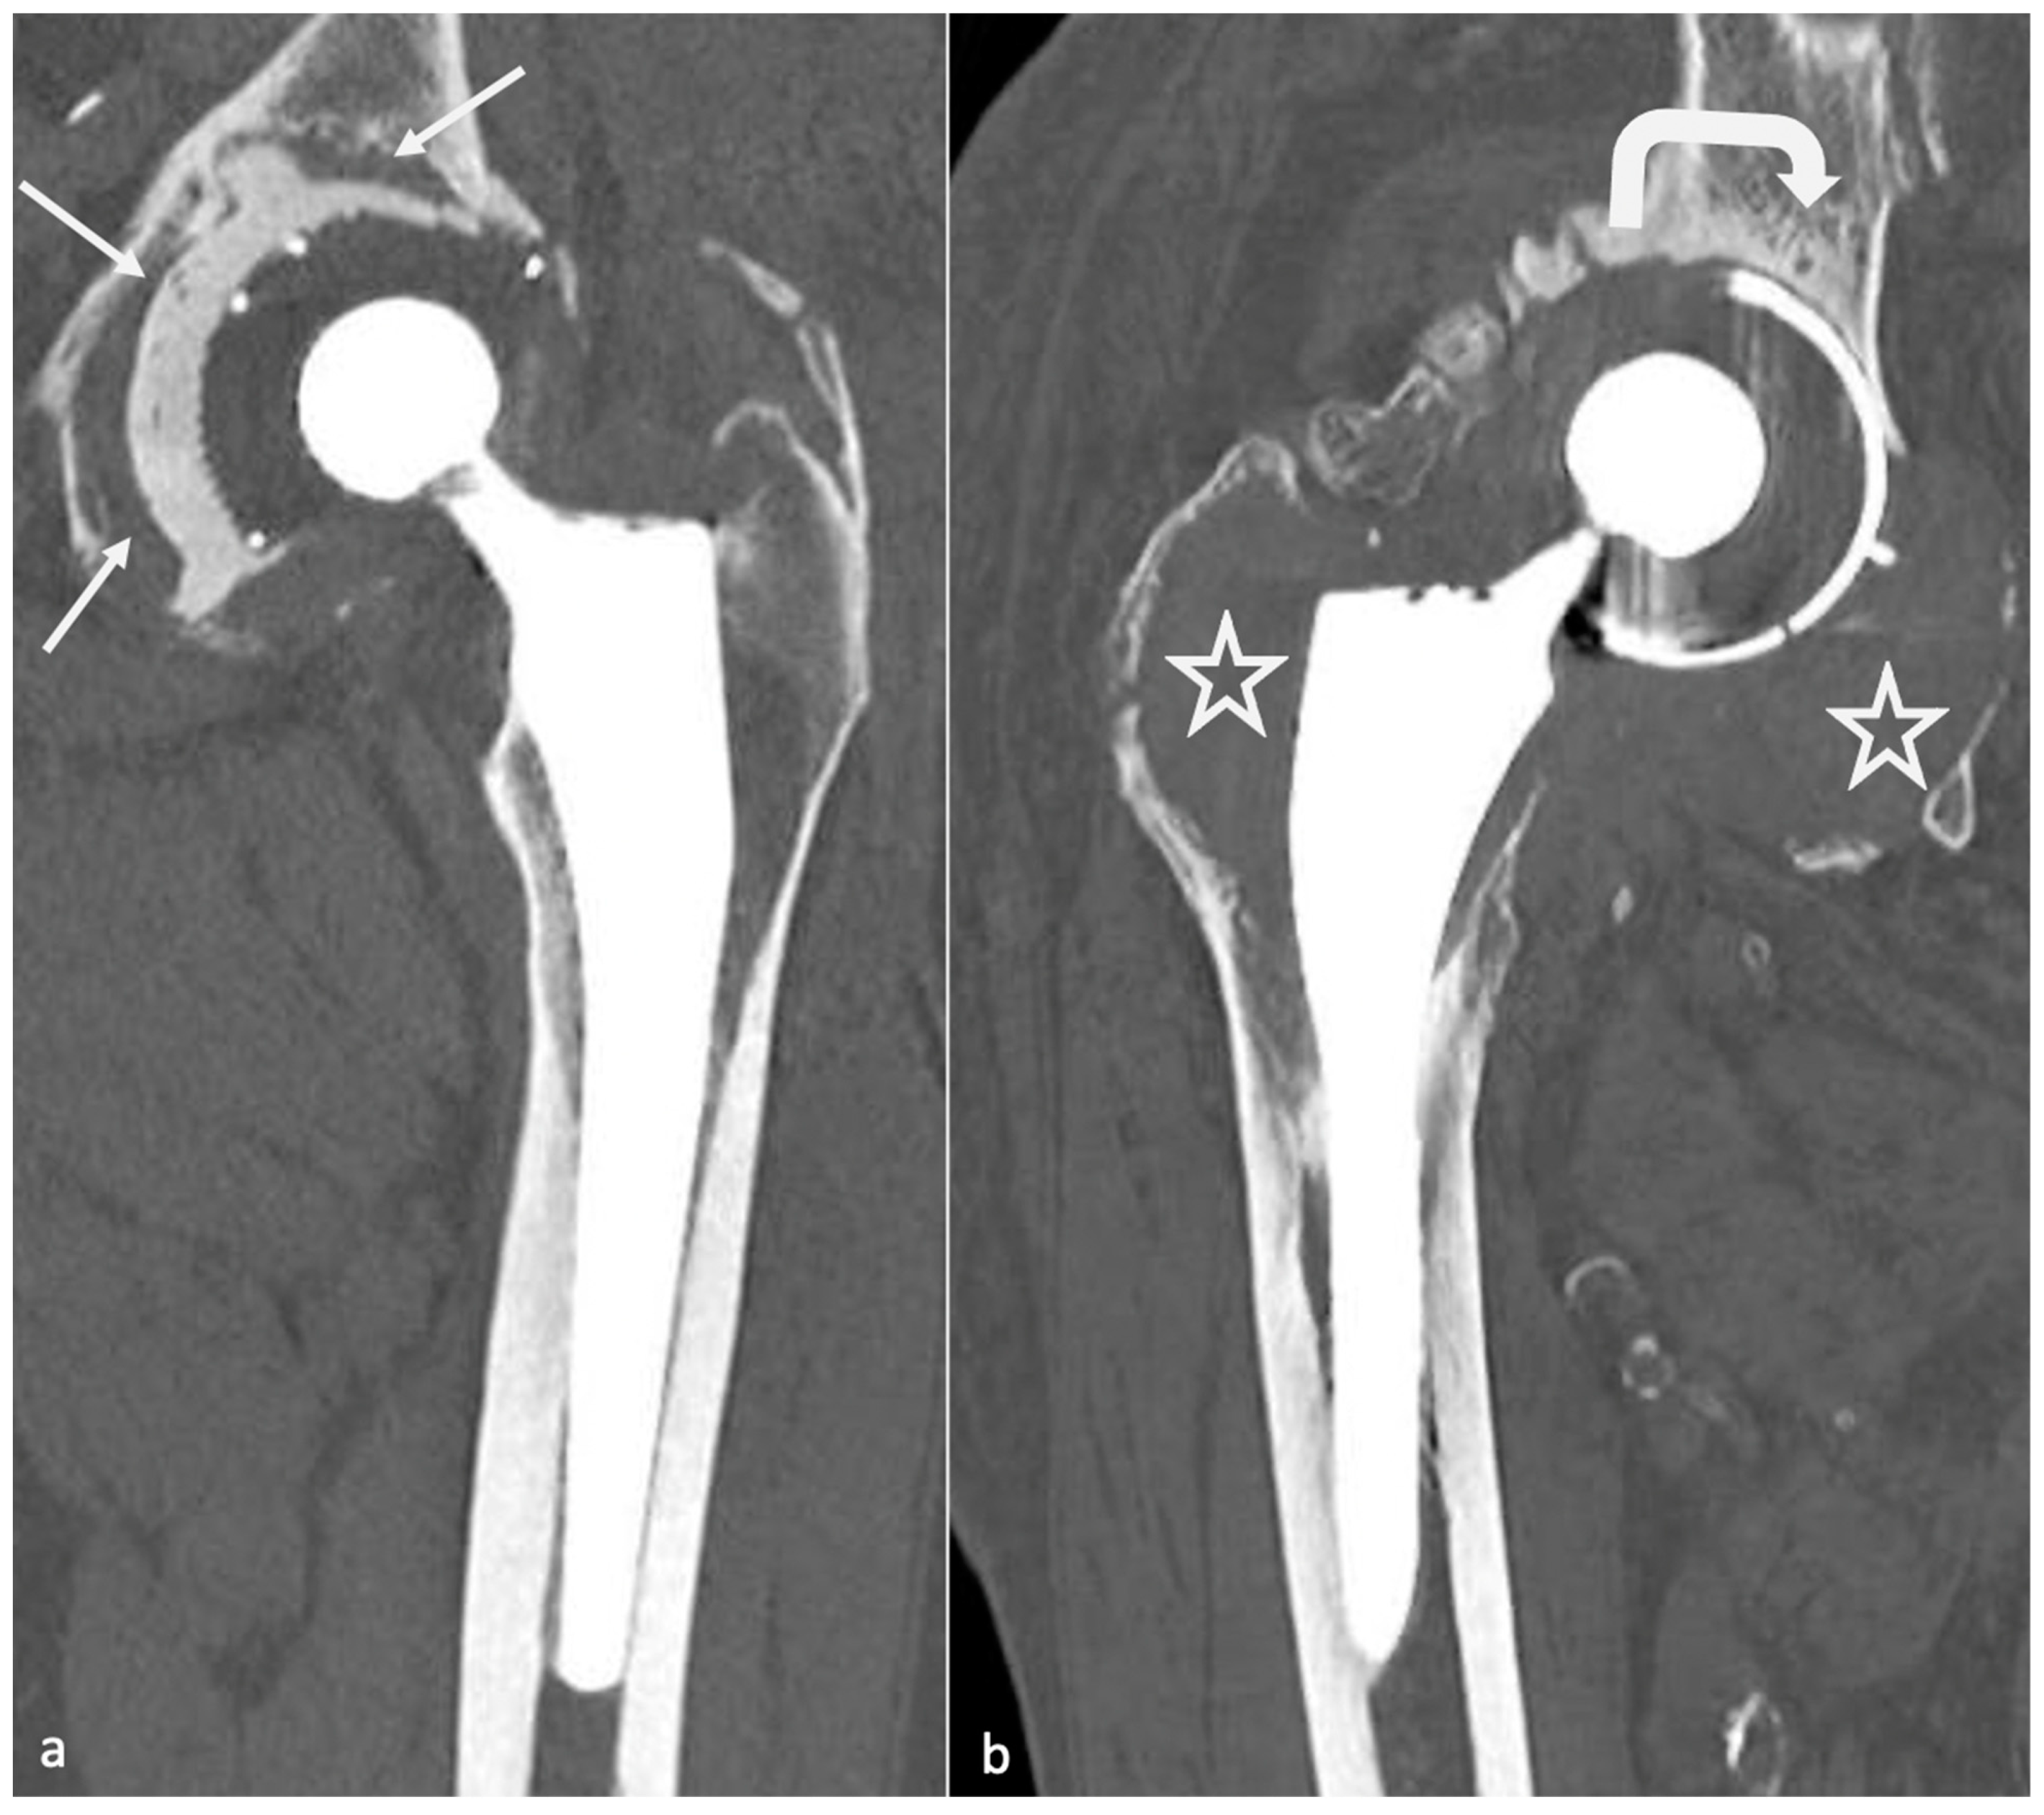

Pseudotumor recurrence in a postrevision total hip arthroplasty with Caliper Hip Arthroplasty To address this we present and evaluate a technique that uses a caliper to control the vertical placement of the femoral component. Achieving appropriate limb length is essential to success in total hip arthroplasty (tha). Achieving stability and equal leg lengths during total hip arthroplasty (tha) is crucial, not only for providing substantial pain. Examples of use include measuring limb. Caliper Hip Arthroplasty.